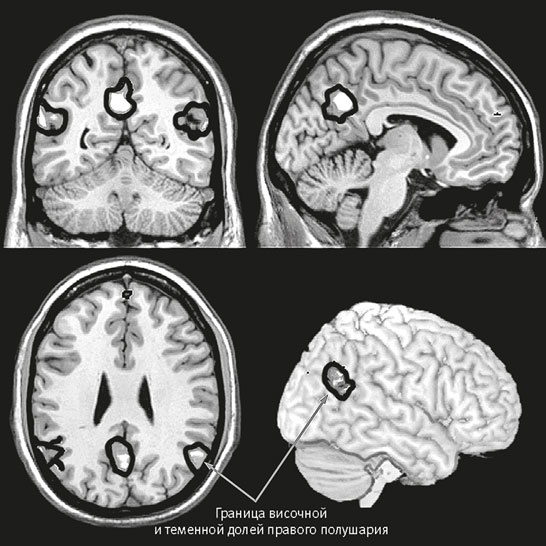

Рис. 25–6. Отделы мозга, активирующиеся, когда мы думаем о том, о чем думает другой человек.

Психолог Кевин Окснер из Колумбийского университета демонстрировал испытуемым небольшие фильмы, показывающие другого человека, и просил подражать его чувствам. Окснер назвал такое подражание, при котором испытуемый не только реагирует на чьи-либо действия и предполагаемые устремления на когнитивном уровне, но и подражает им, активной эмпатией. Эксперимент показал, что для точной интерпретации эмоционального состояния человека, которого испытуемый видел в фильме, требуется активность и участка границы височной и теменной долей, и зеркальных нейронов.